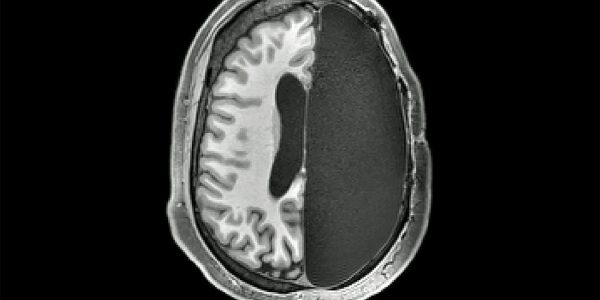

Новое исследование людей, которым не хватает целых половин мозга, дало представление о том, как это возможно, раскрывая замечательную способность человеческого мозга к многозадачности, когда его части буквально отсутствуют.

Шесть участников исследования подвергались пугающе радикальной процедуре удаления одного из полушарий головного мозга в детстве для лечения редкого и экстремального типа эпилепсии. Процедура называется гемисферэктомия и используется только в том случае, если судороги являются «катастрофическими» или лекарства не помогают.

Сравнивая результаты МРТ-сканирования этих участников с другими здоровыми, а также с базой данных из 1482 МРТ снимков, собранных для проекта изучения геномики мозга, Климанн и его коллеги обнаружили, что паттерн активности мозга в состоянии покоя у участников с половиной мозга удивительно похож на паттерн активности здоровых людей.

Но ученые также обнаружили разницу: участники, у которых были полусферэктомии, показали гораздо сильную связь между нейронными сетями мозга.

Это увеличение количества соединений было одинаковым для шести участников и для всех различных сетей — так, например, сеть внимания показала больше подключений к визуальной сети, чем обычно. Схемы подключения между сетями остались такими же, как и у элементов управления, их просто стало больше.

Это увеличение связи между сетями отражает то, как оставшийся мозг компенсирует потерю своей части, чтобы поддерживать когнитивную функцию и сознание, объясняют исследователи в своей статье.